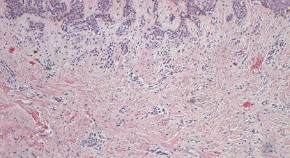

Individuals with the red hair/fair skin phenotype usually carry a polymorphism in the gene encoding the melanocortin 1 receptor (Mc1r) that results in the production of pigment containing a high pheomelanin-to-eumelanin ratio; here it is shown in a mouse model that inactivation of Mc1r promotes melanoma formation in the presence of the Braf oncogene, thus suggesting that pheomelanin synthesis is carcinogenic by an ultraviolet-radiation-independent mechanism.